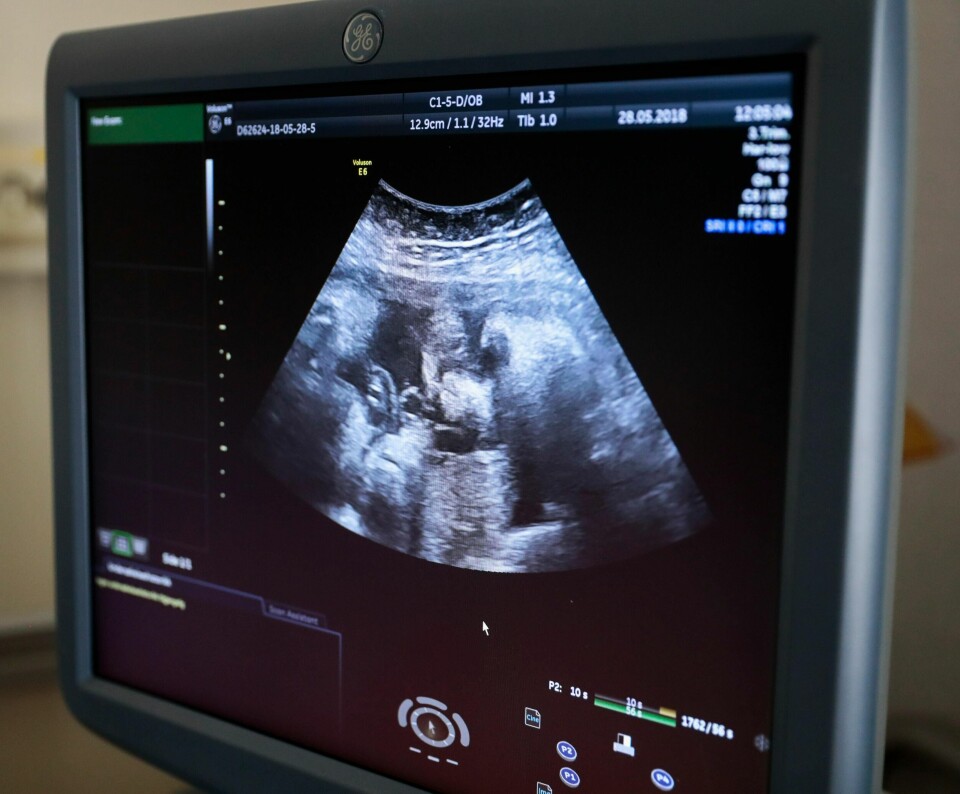

De tre opposisjonspartiene, som sammen har flertall på Stortinget, kunngjorde forrige uke at de har kommet fram til en avtale om en rekke endringer i bioteknologiloven. Blant annet vil de tillate assistert befruktning for enslige, tidlig ultralyd og eggdonasjon.

Hovedtemaet mandag vil være fosterdiagnostikk og preimplantasjonsdiagnostikk (PGD), ettersom det er spørsmål som det sittende rådet ikke har behandlet tidligere.

PGD er gentesting av embryoer, som skal sikre at barn ikke arver en alvorlig sykdom som foreldrene er bærere av. Fosterdiagnostikk gjør det mulig å få informasjon om sykdom og utviklingsavvik hos et foster tidlig i svangerskapet.